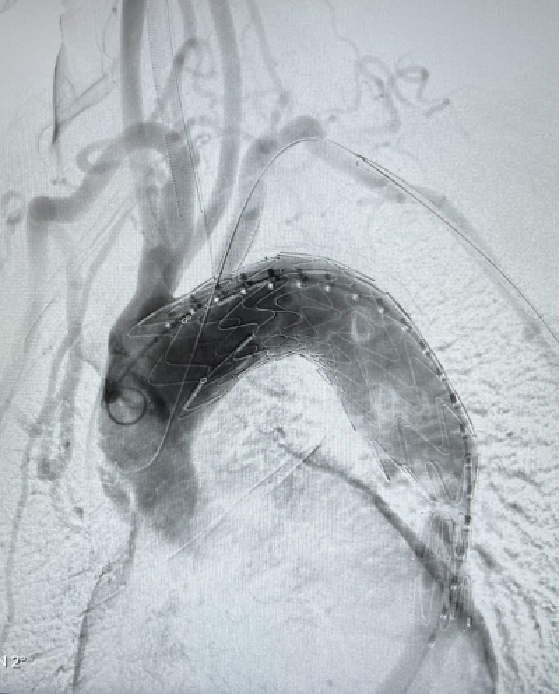

术后实时造影

6个月随访

A、D、G为整体图,其中A为分支支架、D为主支架和分支支架衔接处、G为主支架,B、C、E、F、H、I分别为A、D、G方框处的局部放大图